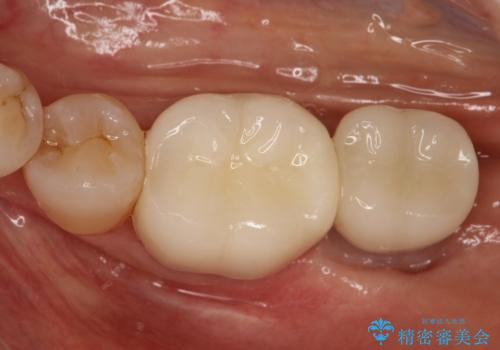

失った歯のインプラントでの咬合回復

- 左下の1番後方の歯が欠損しており、インプラントにて咬合回復する計画としました。

レントゲン・CT撮影により骨の高さがあまりないことがわかり、ショートインプラントを選択しました。

また、清掃性を確保するために歯肉の移植も行うこととしました。